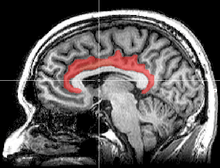

Sagittal MRI slice with highlighting indicating location of the cingulate cortex.